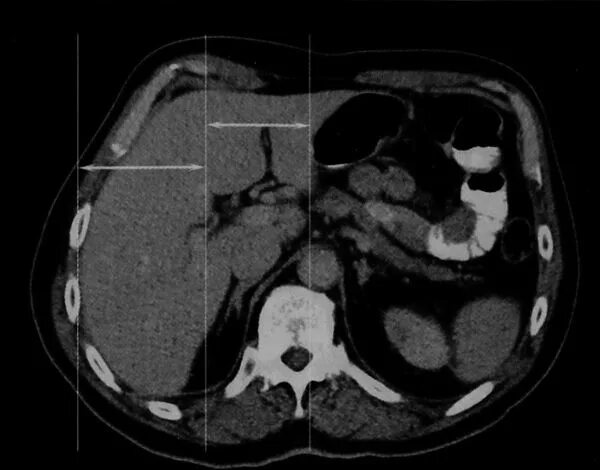

Цирроз печени кт